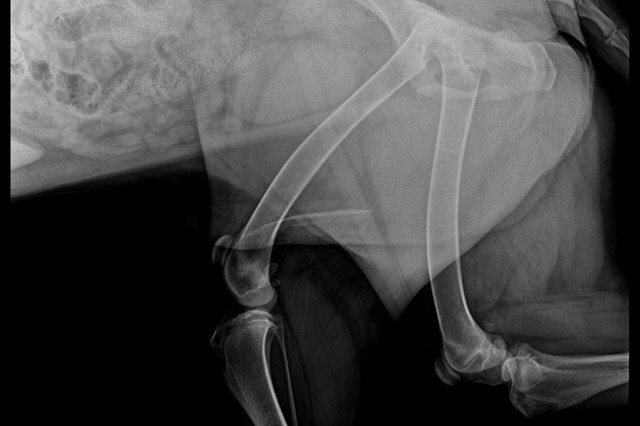

As all puppies do, Chico grew rapidly, and we realized that his hind legs weren't growing with the rest of his body and were extremely under-developed.  After a visit to the vet, we learned that he had a severe case of hip dysplasia. We quickly got him on supplements, medications, and an at-home physical therapy regimen to help with the pain but since he's still a growing pup, these remedies proved no results.

Over the past few weeks, Chico's condition has worsened. He can't run or walk without bunny hopping his hind legs, and needs assistance laying down and getting up. Since our last vet visit with Chico, we learned that the only option for Chico at this point is surgery. He needs a femoral head ostectomy which is a surgical operation to remove the head and neck from the femur. It is performed to alleviate pain, and is a salvage procedure, reserved for condition where pain can not be alleviated in any other way. Chico will need two of these procedures, one for each hip, which will cost $2,500 each.